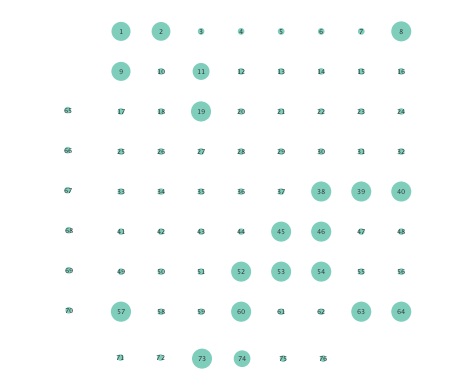

In order to assess the information-routing abilities of brain regions before and after seizure onset, comparisons of the so-termed betweenness centrality were done. Betweenness centrality of a node computes the fraction of shortest paths between all node pairs that traverse the given node, and it is useful to identify the key information transmitting hubs in a network; see e.g., [24] for more details. The per-node betweenness centrality for each inferred network are depicted in Figure 4, with node radii similarly encoding the computed values. Little variation between preictal and ictal betweenness centralities is seen for the linear model (Figures 4 (a) and (b)), while variations are slightly more marked for the K-SVARM, see Figures 4 (c) and (d). It can be seen that modeling nonlinearities reveals subtle changes in information-routing capabilities of nodes between preictal and ictal phases.

Clustering coefficients are generally used to quantify network cohesion, the tendency for nodes to form groups or communities. Comparison of such coefficients between the preictal and ictal phases may reveal differences in cohesive behavior after onset of a seizure. In the present paper, a per-node clustering coefficient is adopted, and it computes the fraction of triangles in which a node participates out of all possible triangles to which it could possibly belong [24]. Note that a triangle is defined as a fully connected three-node subgraph. Figure 5 depicts clustering coefficients per electrode obtained during the ictal and preictal phases of the ECoG time series. While both the linear and nonlinear models yield changes in the computed coefficients, most nodes have lower clustering coefficients upon seizure onset in the networks inferred via the K-SVARM.